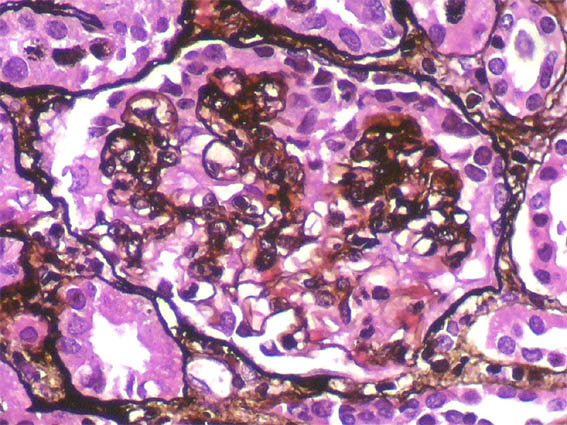

Figure 5. Methenamine-silver, X400.